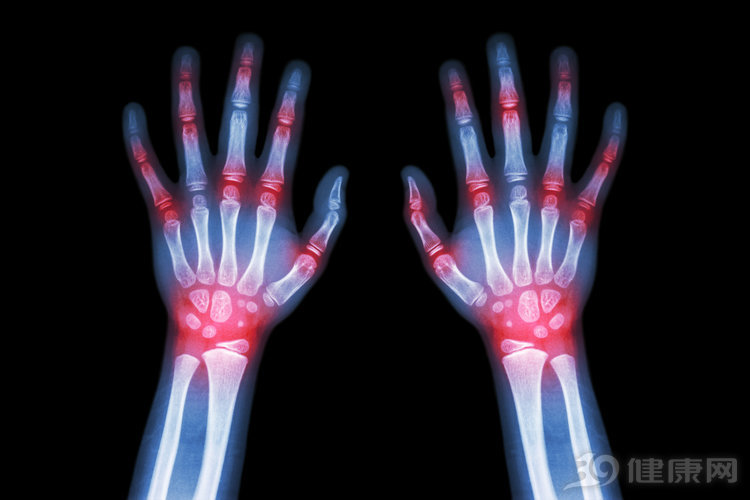

痛风是一种代谢性的疾病,也属于关节炎的一种。嘌呤代谢紊乱而引起的血尿酸增高,痛风病就会因此发作,大多会引起膝关节发生疼痛。除此之外,痛风的患者还会引起体内血尿酸值升高,在患者在 经过两次空腹尿酸检查之后,若男性血尿酸值大于420umol/L,女性大于360umol/L,即可诊断为高尿酸。

如果血尿酸值没有升高,那么其产生的膝盖疼痛可能就是一些风湿性的关节炎。由此可见,痛风是会引起膝盖疼痛的,除此之外还可能会出现关节红热,发烫,同时还伴随皮肤瘙痒的现象。

1.痛风一般是单关节的红肿热痛,疼痛的话一般是一侧疼痛,会呈现红、肿、热,而且痛风一般表现为大脚趾痛,经常都是在半夜发作,跟气候没有多大关系。及时去医院检查,如果是痛风导致的疼痛,那么在B超下,关节软骨上面和下面是分别有两条亮线,临床表现为血尿酸浓度高。痛风患者一般都没有出现损伤状况,疼痛是突然出现的。而且痛风导致的疼痛没有那么容易缓解,即便治疗后还会时不时发病,一旦发病就会感觉到强烈的痛苦感。

3.风湿病一般是膝关节,肩关节,腰等大关节疼痛,与天气变化联系明显,临床检验表现为风湿指标偏高,血沉高,风湿在中医上称之为寒痹,主要是因为风,寒,湿三邪合为一体,影响气血通畅,导致疼痛。